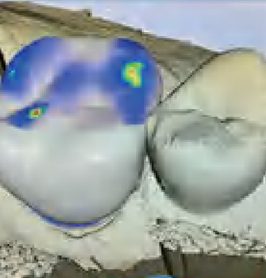

2口内制模 光学取模

模拟蜡型及牙体预备导板,完成标准化微创牙体预备。高精度取像技术直接获取牙齿数据